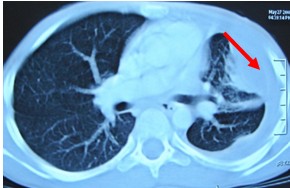

First thing you do is to get the chest x-ray done. The Consult a physician and show him the chest x-ray. If chest x-ray confirms the presence of water, get immediately the ultrasound examination of chest done. If the amount of water collected is between 400 to 500ml millilitres, this water in the chest needs evacuation through syringe-needle under ultrasound or CT- guide. Never allow evacuation of water without the guidance of ultrasound machine, otherwise problem of massive bleeding may occur sometimes.

If the amount of collected water is more than 500 millilitres, consult immediately a thoracic surgeon and have the water in the chest removed with the help of a chest tube. This procedure will prevent the lung from unnecessary trauma and destruction. A chest tube will remove water completely from the chest. Always remember emptying of chest through a chest tube is the simplest and timely method to prevent the destruction of lung.